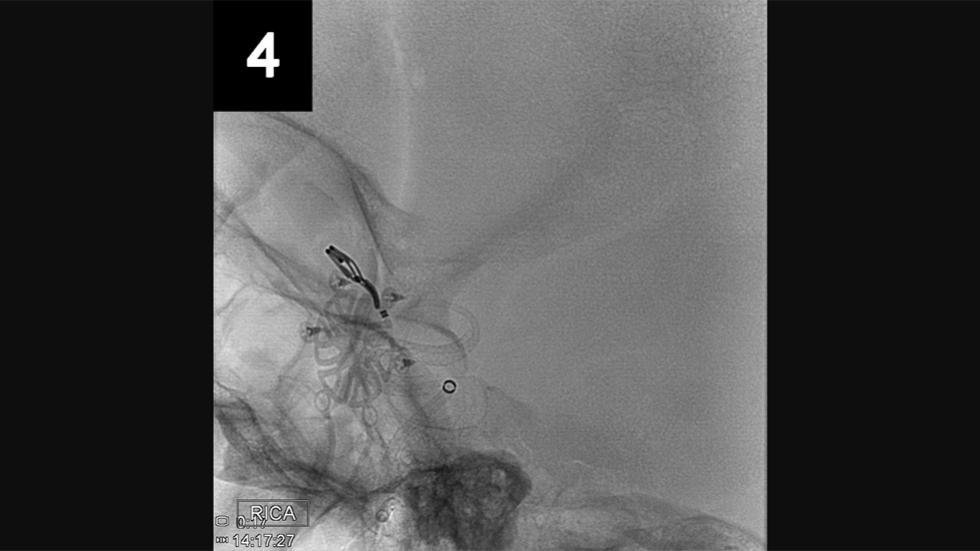

Surgical Clipping

1 of 3

Surgical clipping, also called open microsurgery or craniotomy, is an open surgery performed through a surgical opening in the skull. Using an operating microscope and tiny instruments, the surgeon attaches a small metal clip at the base of the aneurysm. Because blood is prevented from flowing into the aneurysm, the chances of it rupturing are greatly reduced. Recovery time is typically four to six weeks. Pictured: Before Surgical Clipping

Surgical Clip

2 of 3

After Surgical Clipping

3 of 3